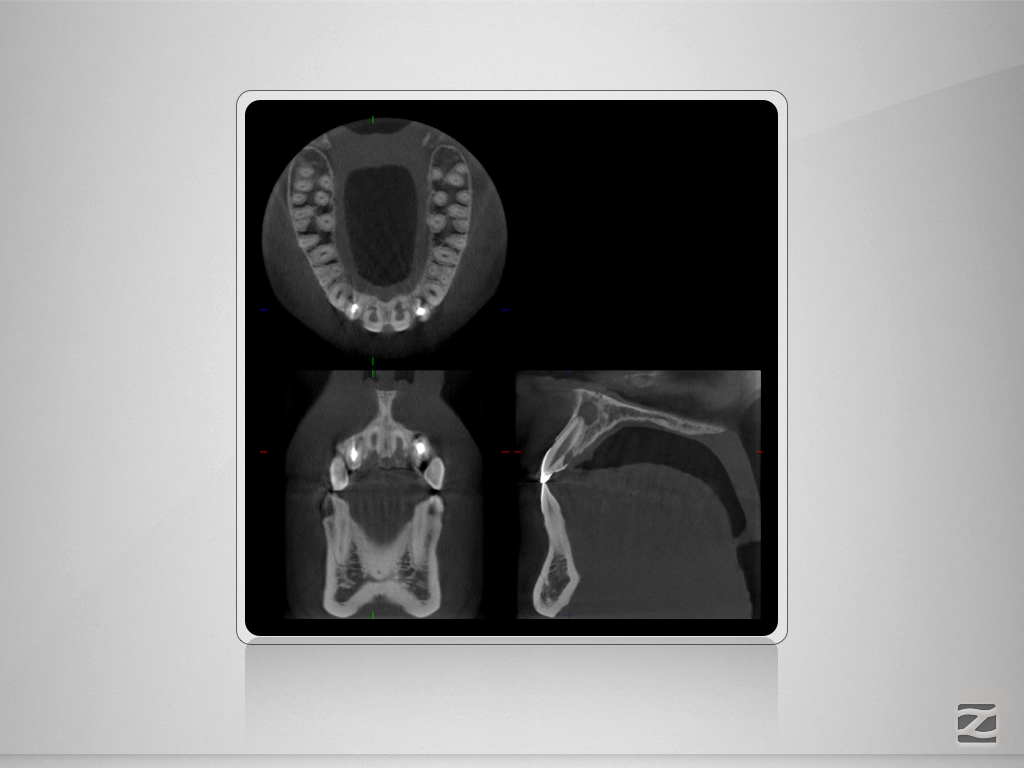

12,11 D.003

1024 × 768

Wer hätte es gedacht , …